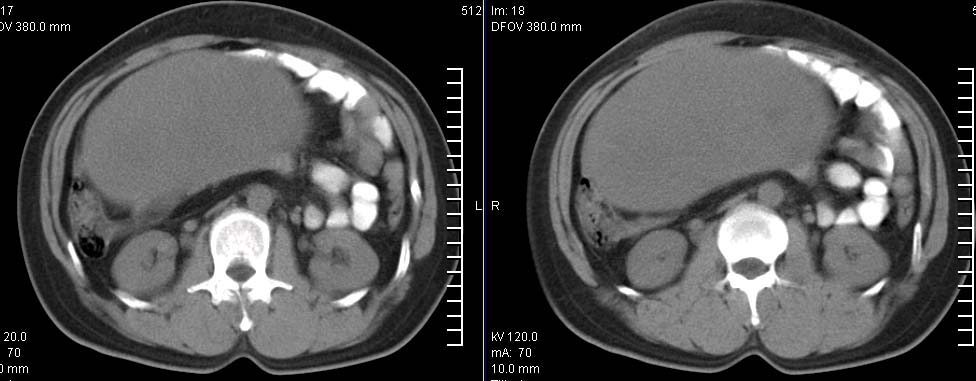

标题: CT9722:卵巢巨大占位,约10*18*21CM大小 [打印本页]

标题: CT9722:卵巢巨大占位,约10*18*21CM大小

卵巢巨大占位,约10*18*21cm大小

肿瘤的密度有点高.和子宫差不多?且和子宫相连呢?我考虑来源于子宫,子宫巨大子宫肌瘤可能性大!(局部有坏死?)

考虑右侧附件来源肿瘤--囊腺瘤可能性大,子宫增大,建议增强扫描.

子宫肌瘤不除外哦。

肿瘤的密度有点高.和子宫差不多?且和子宫相连呢?我考虑来源于子宫,